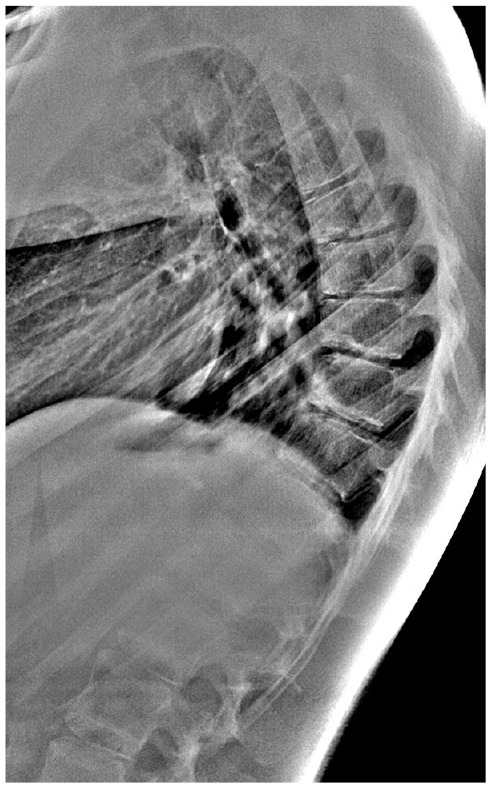

背部疼痛是儿童和青少年中比较常见的主诉。小儿患者的背部疼痛往往是具有挑战性的,有许多众所周知的有机诊断不应该错过。在年幼的儿童中,经常可以发现背部疼痛的器质性原因。然而,年龄较大的儿童和青少年的背痛通常是“非特异性的”。儿童背痛的鉴别诊断包括肿瘤、发育和炎症。基本步骤应包括深入的记忆、系统的体格检查和标准的脊柱x线片(前后位和侧位)。然而,先进的诊断成像和实验室研究应包括当指,以避免遗漏或延误严重的诊断。如果需要其他类型的影像学检查(磁共振成像、计算机断层扫描、骨扫描或单光子发射计算机断层扫描),则应以诊断怀疑为指导。

Back pain is a relatively common complaint in children and adolescents. The pediatric patient presenting with back pain can often be challenging, and there are many well-known organic diagnoses that should not be missed. In younger children, an organic cause of back pain can often be found. However, back pain in older children and adolescents is often "non-specific." The differential diagnosis of back pain in children includes neoplasms, developmental, and inflammatory conditions. Basic steps should include an in-depth anamnesis, a systematic physical examination, and standard spine radiographs (anteroposterior and lateral). Nevertheless, advanced diagnostic imaging and laboratory studies should be included when indicated to avoid missing or delaying a serious diagnosis. If other types of imaging tests are necessary (magnetic resonance imaging, computed tomography, bone scan, or single photon emission computed tomography), they should be guided by diagnostic suspicion.